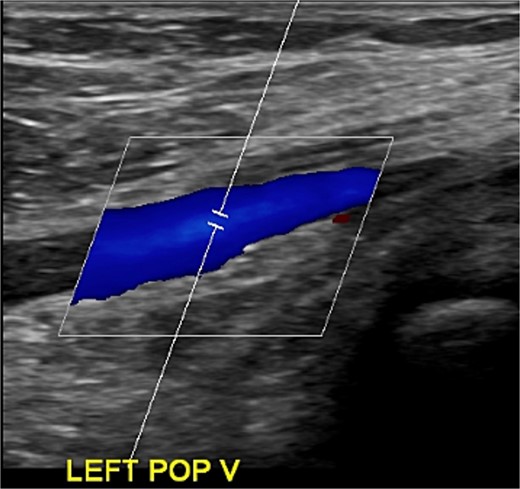

Despite initial improvement, the patient’s CRP stabilized at 5.5 μg/ml 6 days post-operatively. Consequently, a repeat I&D with antibiotic bead placement was performed on postoperative Day 7. The patient’s condition improved, with undetectable CRP levels at discharge 14 days after initial hospitalization. Four weeks post-discharge, a repeat venous ultrasound of the affect extremity was performed, demonstrating resolution of the DVT (Fig. 2). In total, the patient received 18 weeks of outpatient oral antibiotic therapy and 9 weeks of anticoagulation therapy. Six months post-hospitalization, the patient was asymptomatic and cleared to return to full activity. After 1-year post-discharge, final radiographs demonstrated no osseous abnormalities, the patient remained asymptomatic, and was released from clinic (Figs 3 and 4).

Ultrasonography obtained in January of 2023 demonstrating resolution of DVT.